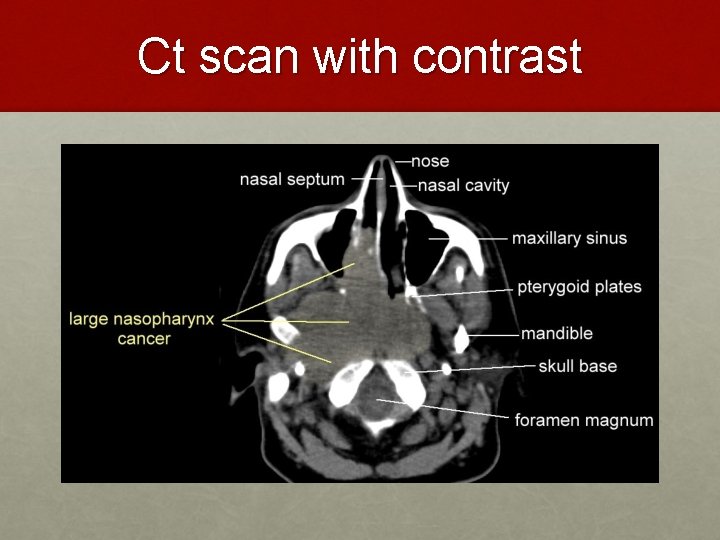

Ct scan with contrast